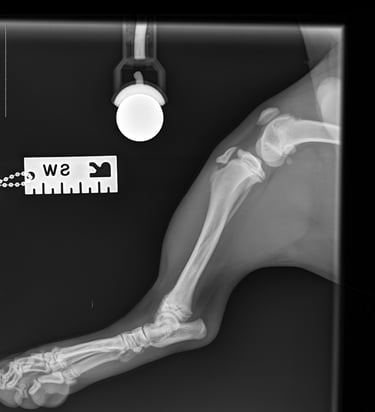

Lateral radiographs revealed a complete avulsion of the left tibial crest (Fig. 1), along with a mild lesion at the distal pole of the patella. For comparison, a lateral view of the right limb is included, demonstrating a normal appearance of the tibial crest growth plate (Fig. 2).

Fig. 2